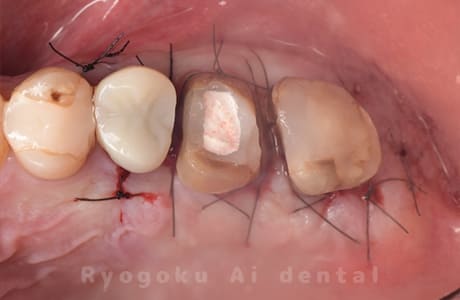

Case09

-

- 原因

- 左上6番重度カリエス

- 治療内容

- クラウンレングスニング

- 治療費用

- 44,000円(根管治療、補綴は別途費用)

他院で抜歯と判断された歯です。クラウンレングスニングを行い、保存を試みました。現在も問題なく被せ物が入り、使用できてます。

<リスク・副作用>

手術後は痛み、腫れ、痺れ、青あざなどの副作用が生じます。痛みは痛み止めを処方しますが、腫れ、青あざは1週間程度生じる場合があります。また、部位によっては神経の走行が複雑で、痺れが残り、長期的にお薬を処方する場合があります。